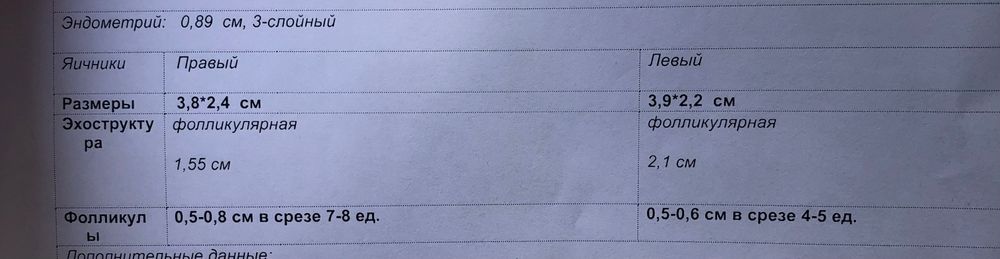

Сегодня с мужем сдавали анализы для вми, поставила последний укол Менопур и решила фолликулометрию сделать . Фото ниже.

Теперл думаю , ставить ли укол хгч, в левом уже созрел фоллик((

Уже хороший,зрелый и эндометрий трёхслойный,думаю завтра самое то кольнуть) в день на 2 мм растёт ,как раз завтра будет его пик

Juliya, второй маловат ,не успеет вырасти,а этот самое то. У меня в этот раз 19 дорос, врач отправила на следующей день ставить укол , только сказала обязательно к вечеру)

Я б сегодня вечером уколола. Им ещё 36 часов в среднем дозревать до О, как раз и мелкий подтянется быстрее и одновременно лопнут.